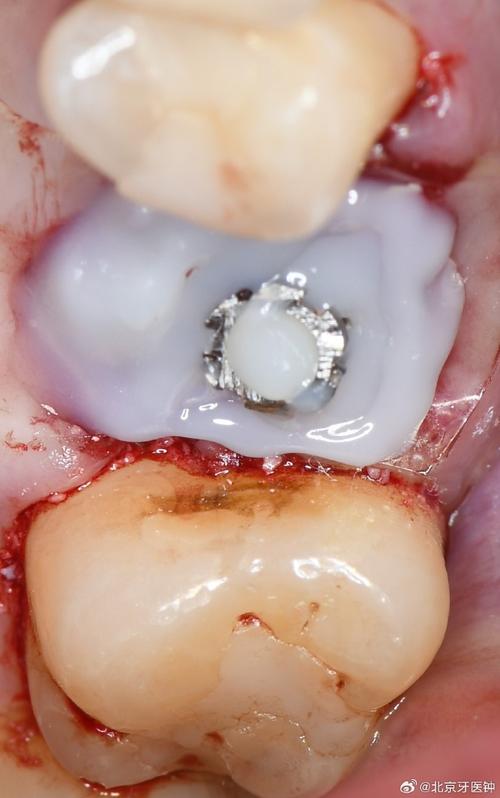

- 植骨: 在种植区域植入骨移植材料(自体骨、异体骨、人工骨等),引导新骨生长,增加骨量,可能需要几个月的愈合期。

- 上颌窦提升术: 对于上颌后牙区骨量高度不足,接近或进入上颌窦的情况,需要将上颌窦底黏膜推起,在骨膜和黏膜之间填入骨移植材料,增加骨高度,分为内提升和外提升两种方式。